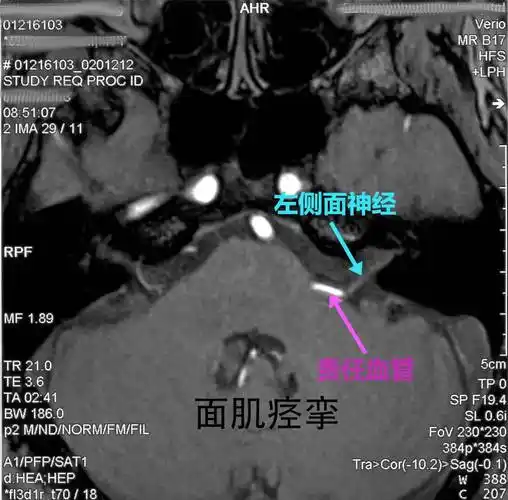

神经外科主任姬馨彤教你如何通过ct怎样判断面肌痉挛,三叉神经痛和脑